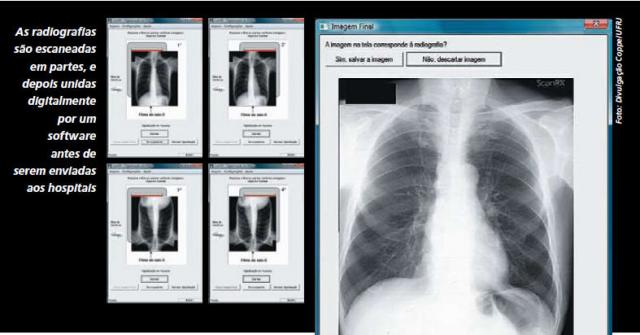

O profissional do posto de saúde de Piraí escaneia o filme do exame de raios X convencional em até quatro partes, se for necessário, para ajustá-lo à dimensão do scanner. O usuário é guiado por uma interface que informa o número de passos e movimentos necessários para a aquisição correta da imagem parcial e também mostra como o filme deve ser exposto no scaner para evitar erros na identificação da imagem. Essa imagem digitalizada do exame é comprimida para viabilizar sua transmissão pela internet, mesmo em locais de conexão lenta, e anexada a um formulário eletrônico, desenvolvido no Núcleo RJ do Telessaúde Brasil, e enviada a uma equipe de teleconsultores dos serviços de radiologia, como a do Hospital Universitário Clementino Fraga Filho, da UFRJ. Após análise, a resposta é devolvida no mesmo formulário para que o médico possa obter o diagnóstico final e medicar o paciente, se necessário na hora. Desta maneira, é acessível a qualquer usuário, que não precisa de nenhum conhecimento especial em informática ou radiologia.